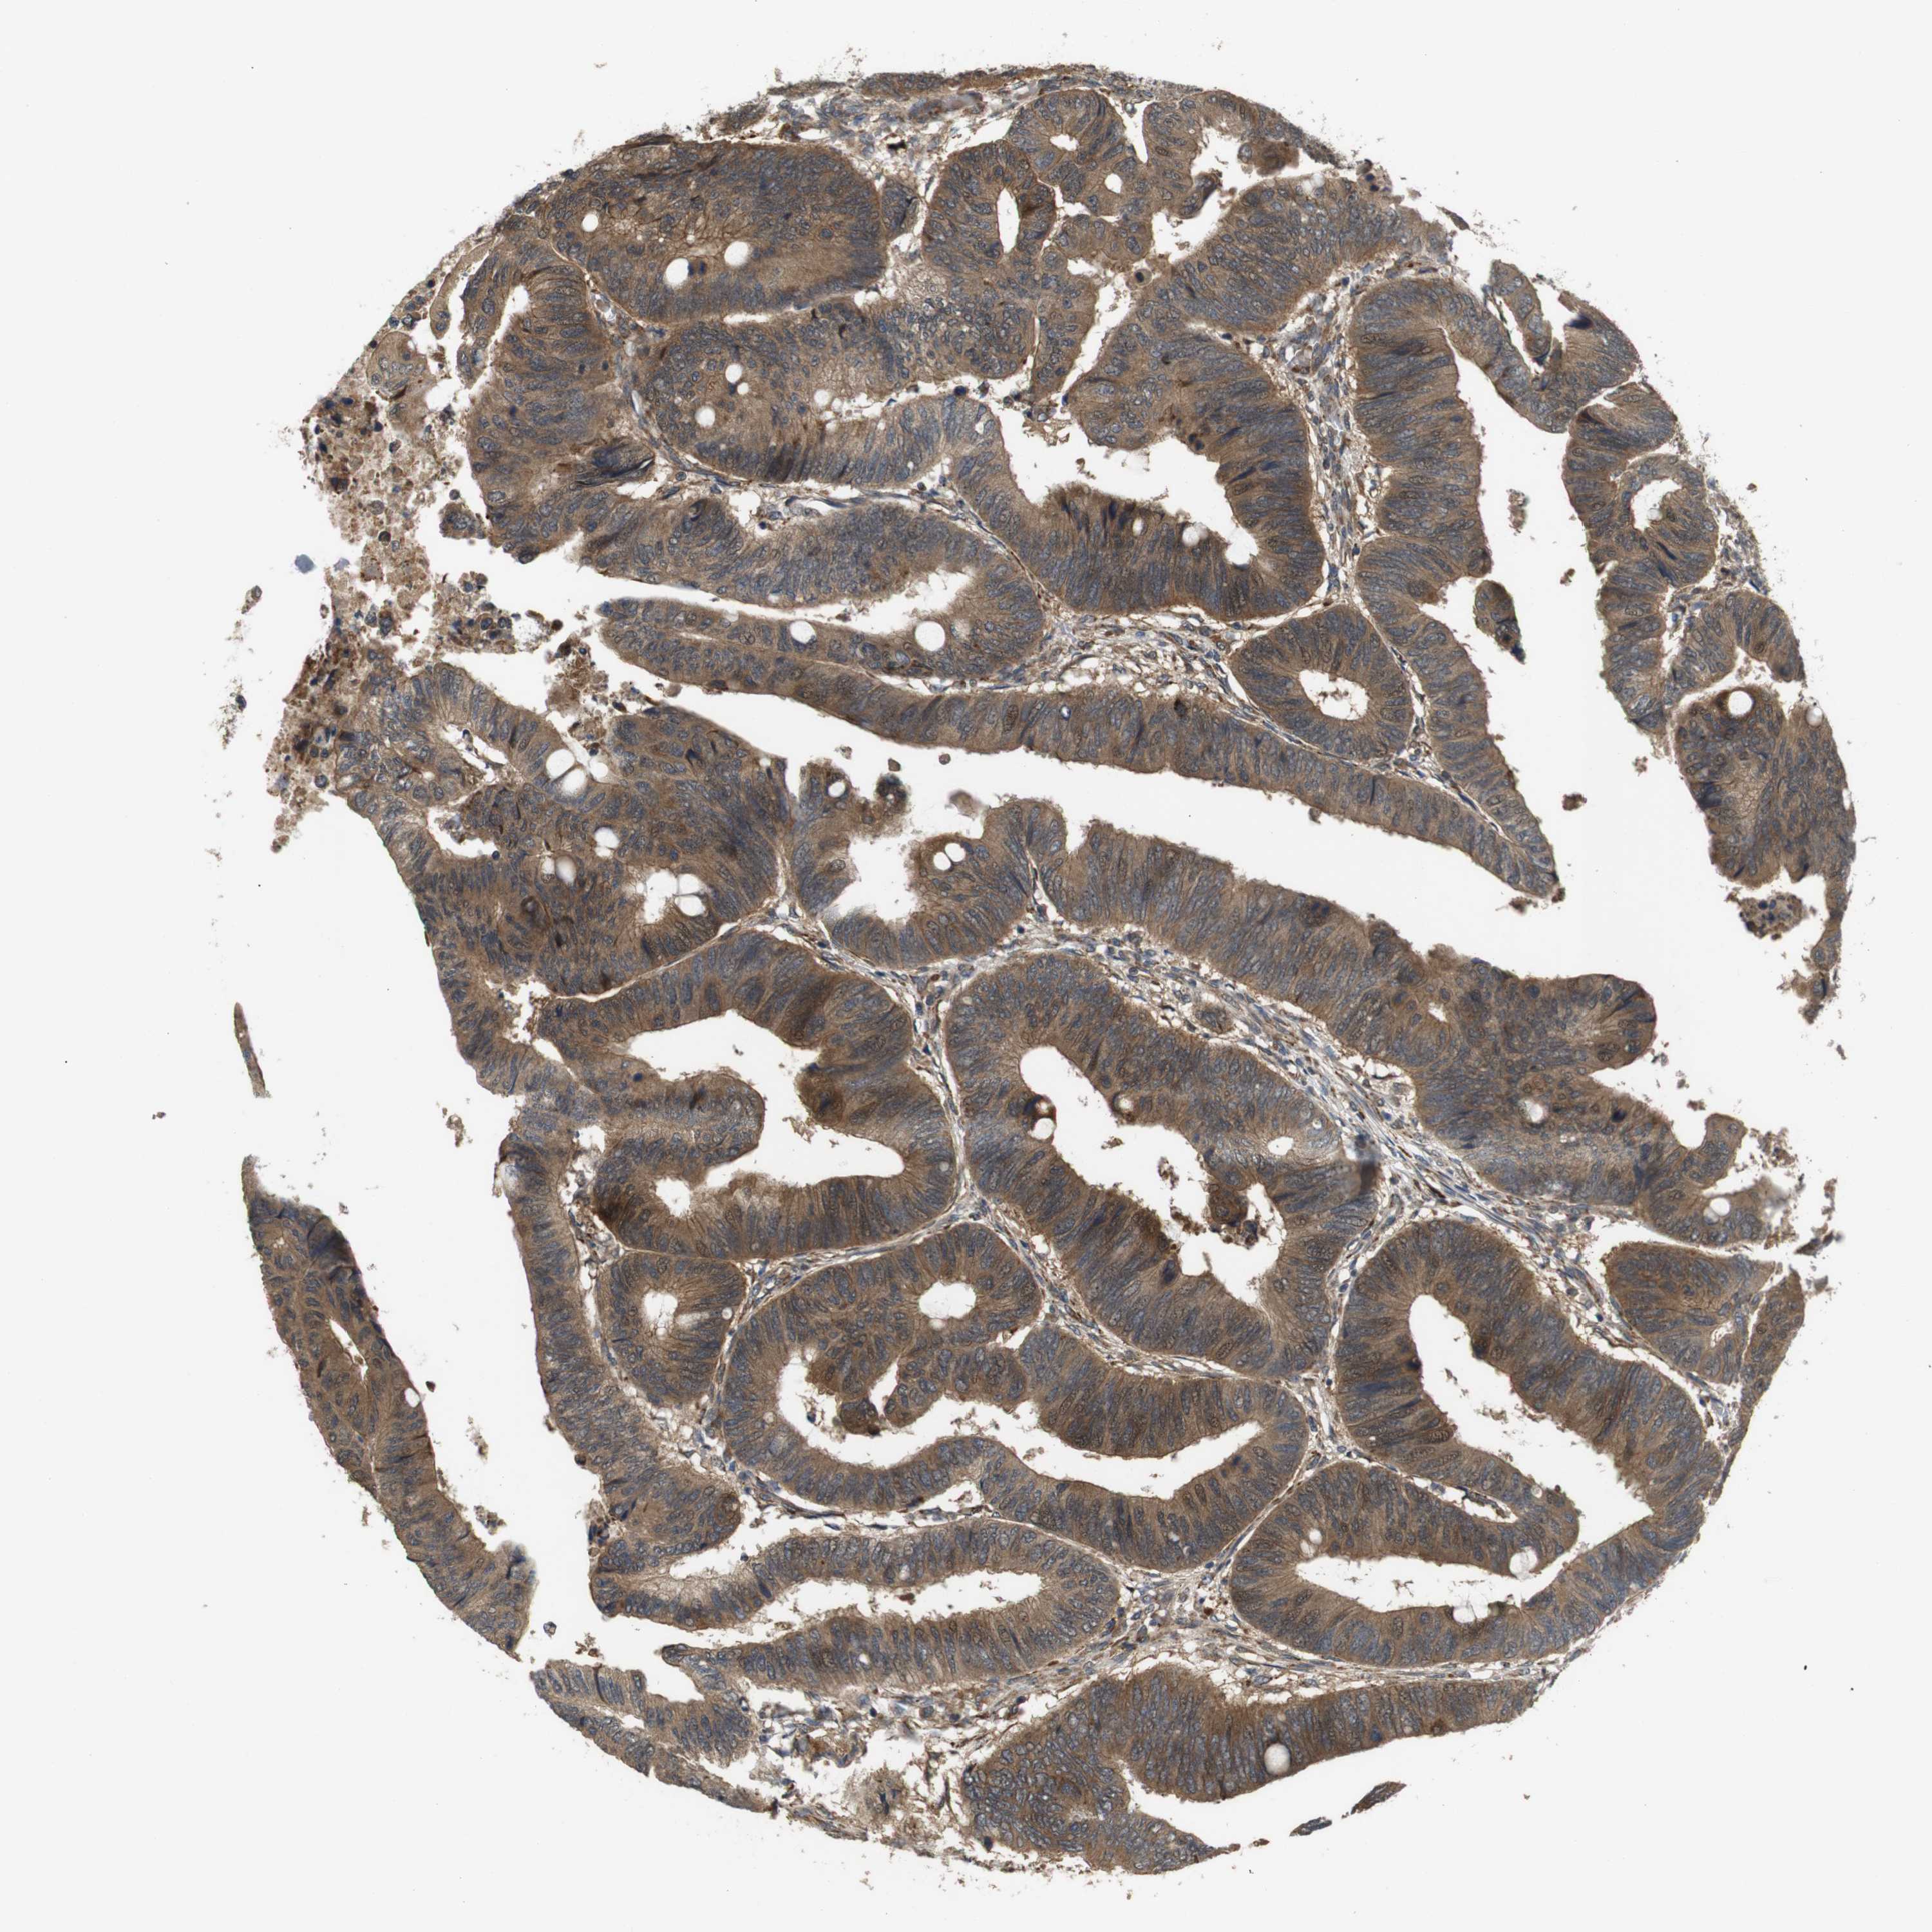

CANCER COLORECTAL CANCER Show tissue menu

Colorectal cancer

Human cancer

Rectum adenocarcinoma